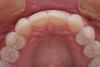

Figure 10  The final full smile of case two. Veneers cemented with NX3, Kerr.

Figure 10

Figure 11  Final lateral view of case two. Note the restoration of the proper incisal plane created by adding back the necessary contours. The premolar was restored with the contour of a canine tooth.

Figure 11

Further orthodontic intervention was declined by the patient. Therefore, to meet the patient’s esthetics goals and the necessary functional requirements, a restorative option of stacked porcelain veneers was pursued. During the treatment-planning phase of the restorative process, a diagnostic wax-up was created to allow the buccal cusps of the premolar to mimic the contour of a canine. This allowed immediate posterior disclusion, which decreased the activity of the elevator muscles. Bis-acrylic temporary restorations (Fill-In, Kerr) were created off the diagnostic wax-up, thus allowing a period to test the new anterior guidance (Figure 9). After approximately 6 weeks of the patient testing of the new functional contours, impressions of the provisional restorations were taken. Stents were then made from these models to allow duplication of the provisional contours in the porcelain restorations (Figure 10 and Figure 11).